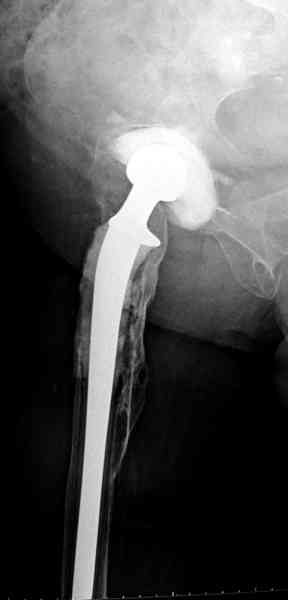

Представляю вашему вниманию снимки (прошу прошения за качество снимков) больной 48 лет с ревматоидным артритом, которой был сделан тотальный эндопротез справа,

контрольный снимок сделали только на 21день после операции (№1) и с интервалом 5 дней второй снимок (№2)

Судя по всему, произошел раскол наружной стенки бедра и ножка находится вне костного канала. В таком случае

решение одно - удаление ножки и установка новой в расчете на дистальную фиксацию. Конктреную модель подсказать тяжело из-за низкого качества Р-грамм.